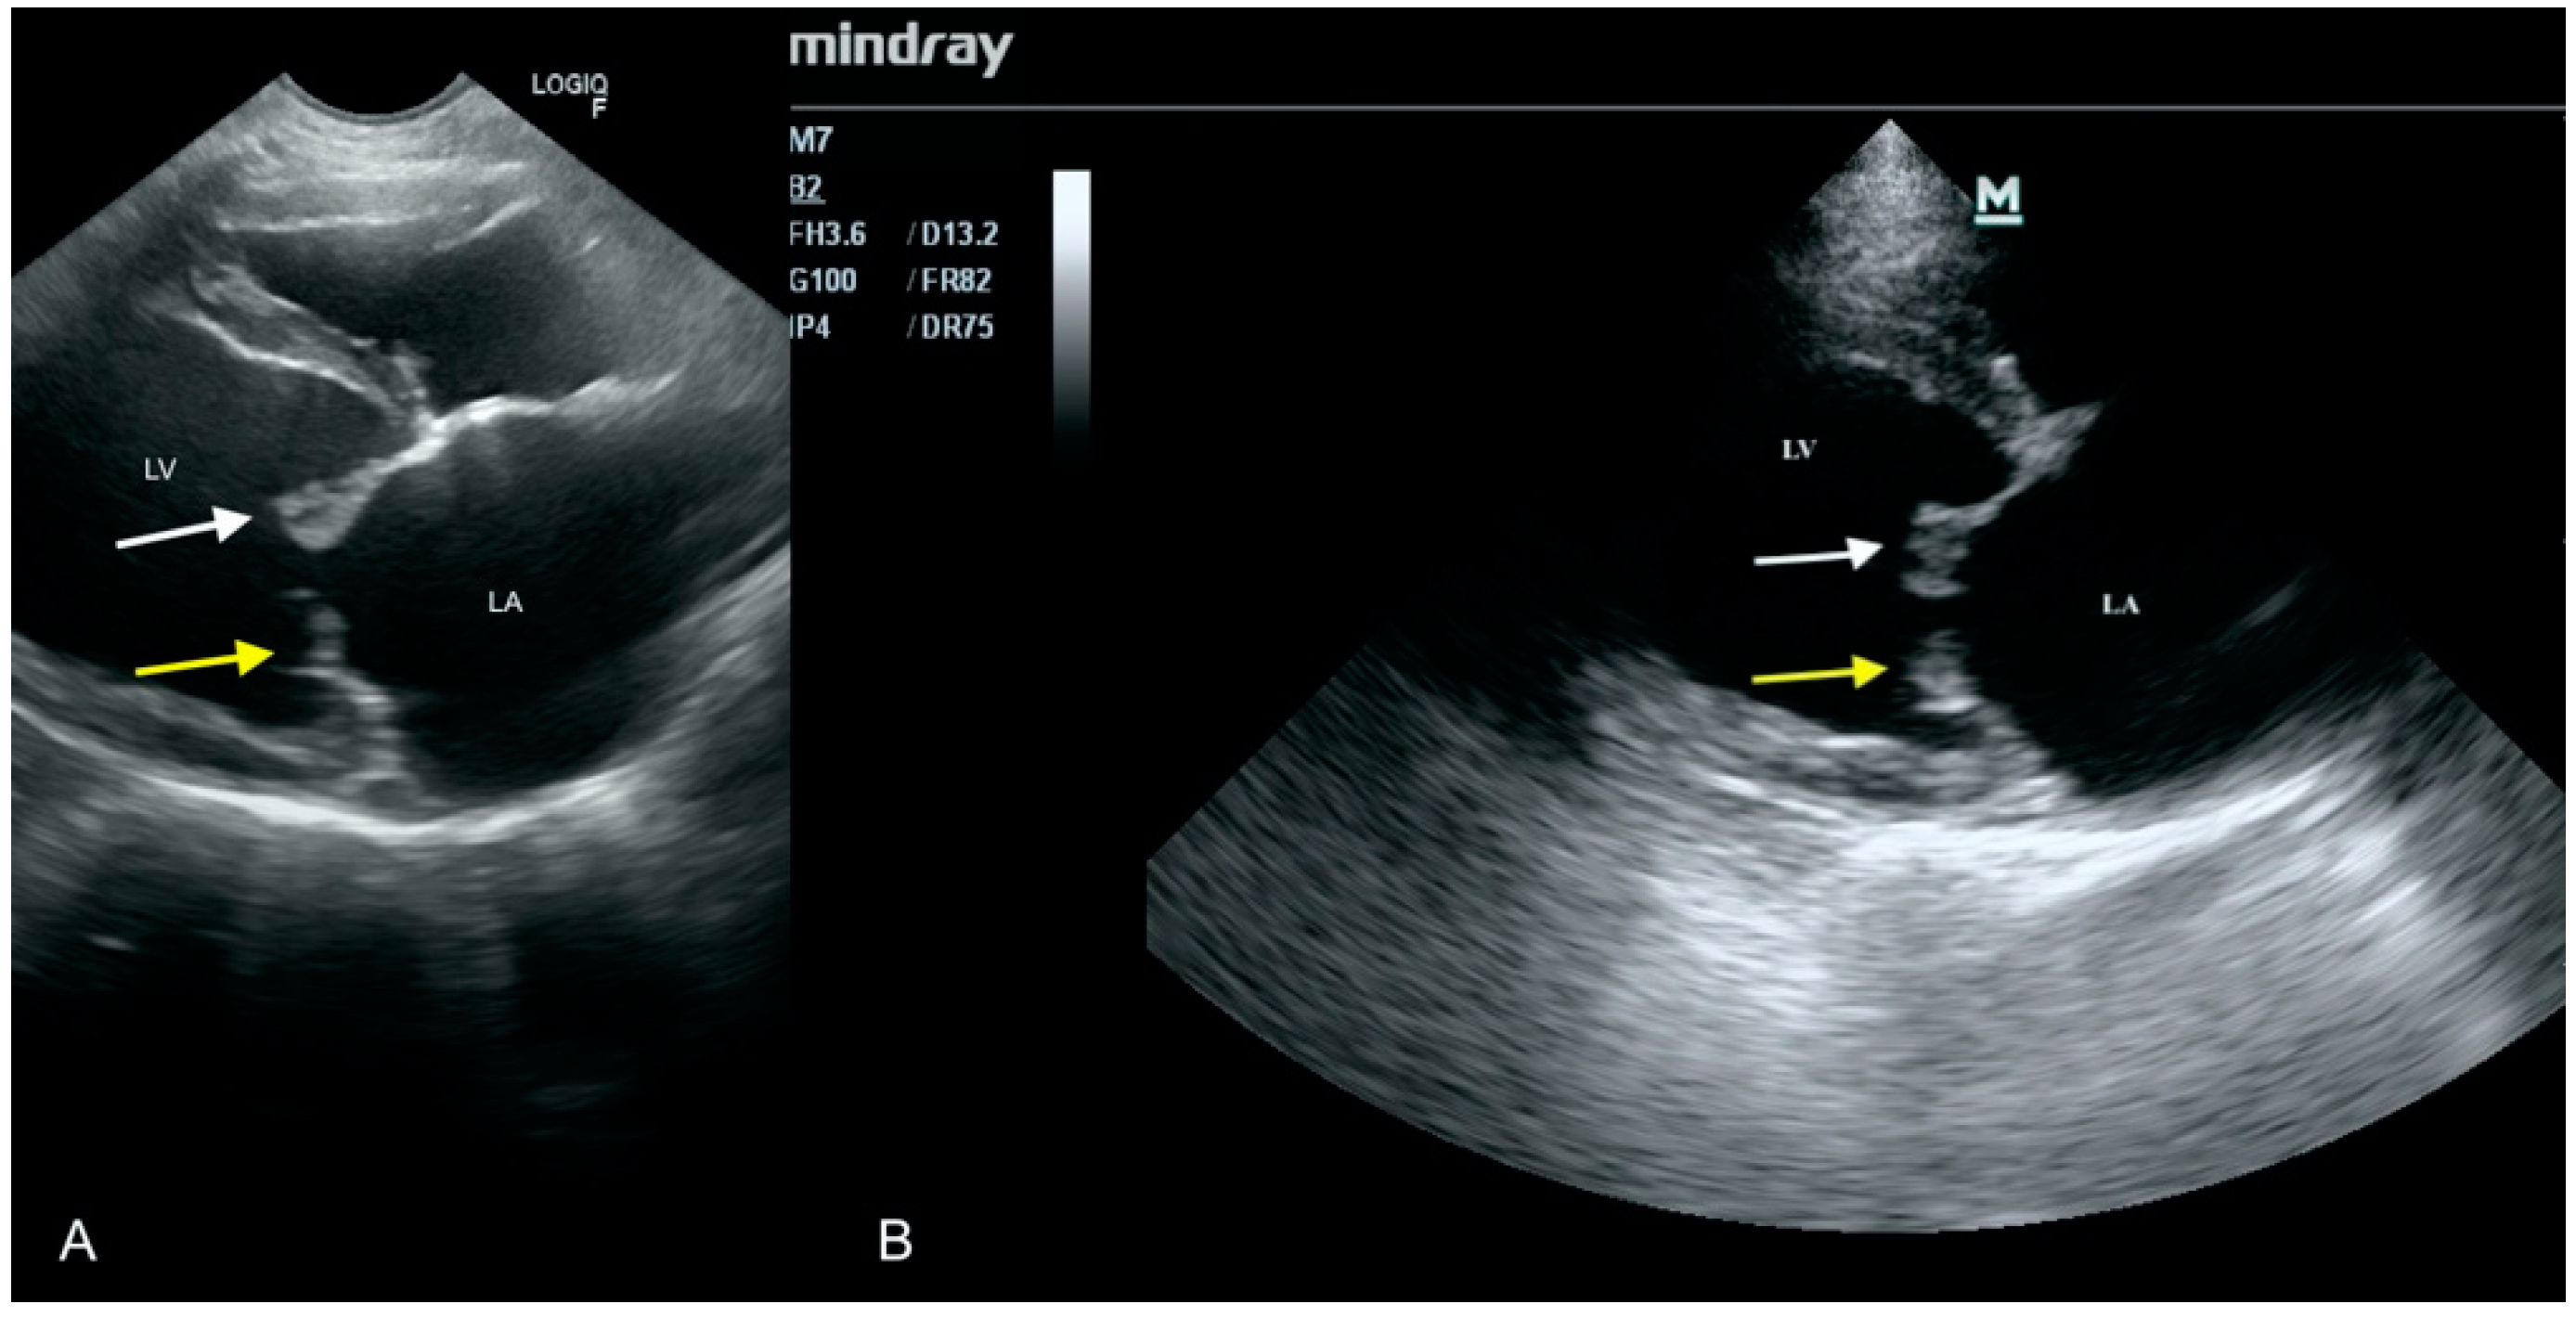

3.4. Case No. 4